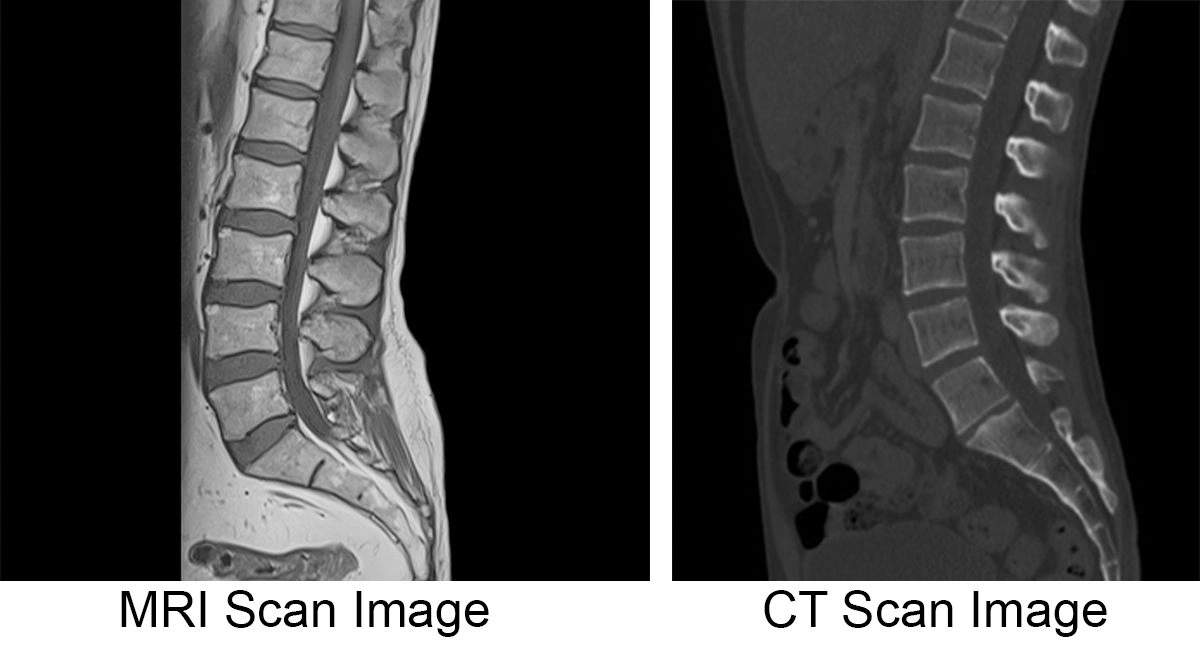

تشخیص آرتروز ستون فقرات یک فرآیند چند مرحلهای است که به بررسی دقیق علائم بیمار، انجام معاینات فیزیکی و استفاده از روشهای تصویربرداری و آزمایشگاهی نیاز دارد. پزشکان برای تشخیص این بیماری ابتدا تاریخچه پزشکی بیمار بررسی میکنند و اطلاعاتی مانند: مدت زمان بروز علائم، شدت درد، عوامل تشدیدکننده و سابقه خانوادگی را ارزیابی میکنند. پس از آن، معاینه فیزیکی برای بررسی وضعیت عضلانی، انعطافپذیری، میزان درد در حرکات خاص و تاثیر بیماری بر عملکرد روزمره بیمار انجام میشود. سپس، پزشک برای تایید تشخیص از روشهای تصویربرداری مانند: اشعه ایکس، امآرآی و سیتیاسکن استفاده میکند. در برخی موارد، آزمایش خون برای بررسی وجود بیماریهای خودایمنی مانند آرتریت روماتوئید یا تشخیص التهابات مفصلی نیز تجویز میشود. در ادامه روشهای تشخیص آرتروز ستون فقرات را بررسی میکنیم.

امآرآی (تصویربرداری رزونانس مغناطیسی) یک روش تصویربرداری پیشرفته است که به پزشکان امکان میدهد جزئیات بیشتری از وضعیت ستون فقرات و بافتهای نرم مانند: دیسکها، عصبها و رباطها را نسبت به دیگر روشها مشاهده کنند. برخلاف اشعه ایکس که فقط تصاویری از استخوانها میگیرد، امآرآی میتواند تغییرات در بافتهای نرم مانند: تخریب غضروفها، بیرونزدگی دیسک یا فشردگی اعصاب را نشان دهد. این روش در مواردی که پزشک به آسیب بافتهای نرم مشکوک است یا اگر آرتروز ستون فقرات روی اعصاب تاثیر گذاشته باشد، بسیار مفید است. همچنین میتواند اطلاعات دقیقی در مورد باریک شدن فضاهای بین مهرهها، فشار روی عصبها و سایر مشکلات مربوط به دیسکها ارائه دهد.

سیتیاسکن یک روش تصویربرداری پیشرفته است که ترکیبی از تصاویر اشعه ایکس و تکنولوژی کامپیوتری است. این تکنیک به پزشک اجازه میدهد که تصاویری سهبعدی از ستون فقرات بهدست آورد که برای شناسایی دقیقتر مشکلات استخوانی و مفصلی مفید است. این روش در مواردی که اشعه ایکس قادر به ارائه جزئیات کافی نباشد، کاربرد دارد. همچنین برای بررسی آسیبهای استخوانی، شکستگیهای مهرهها و تغییرات در ساختار استخوانی مفید است. با توجه به توانایی سیتیاسکن در ایجاد تصاویری سهبعدی، پزشک میتواند بهدقت محل آسیب را تشخیص دهد و تغییرات در ساختار استخوانی که میتوانند به دلیل آرتروز ایجاد شده باشند را بررسی کند. از آنجا که سیتیاسکن معمولا برای تشخیص مشکلات استخوانی استفاده میشود، در مواردی که پزشک به دنبال بررسی آسیب به بافتهای نرم باشد، از امآرآی بهعنوان روش تکمیلی استفاده میکند.